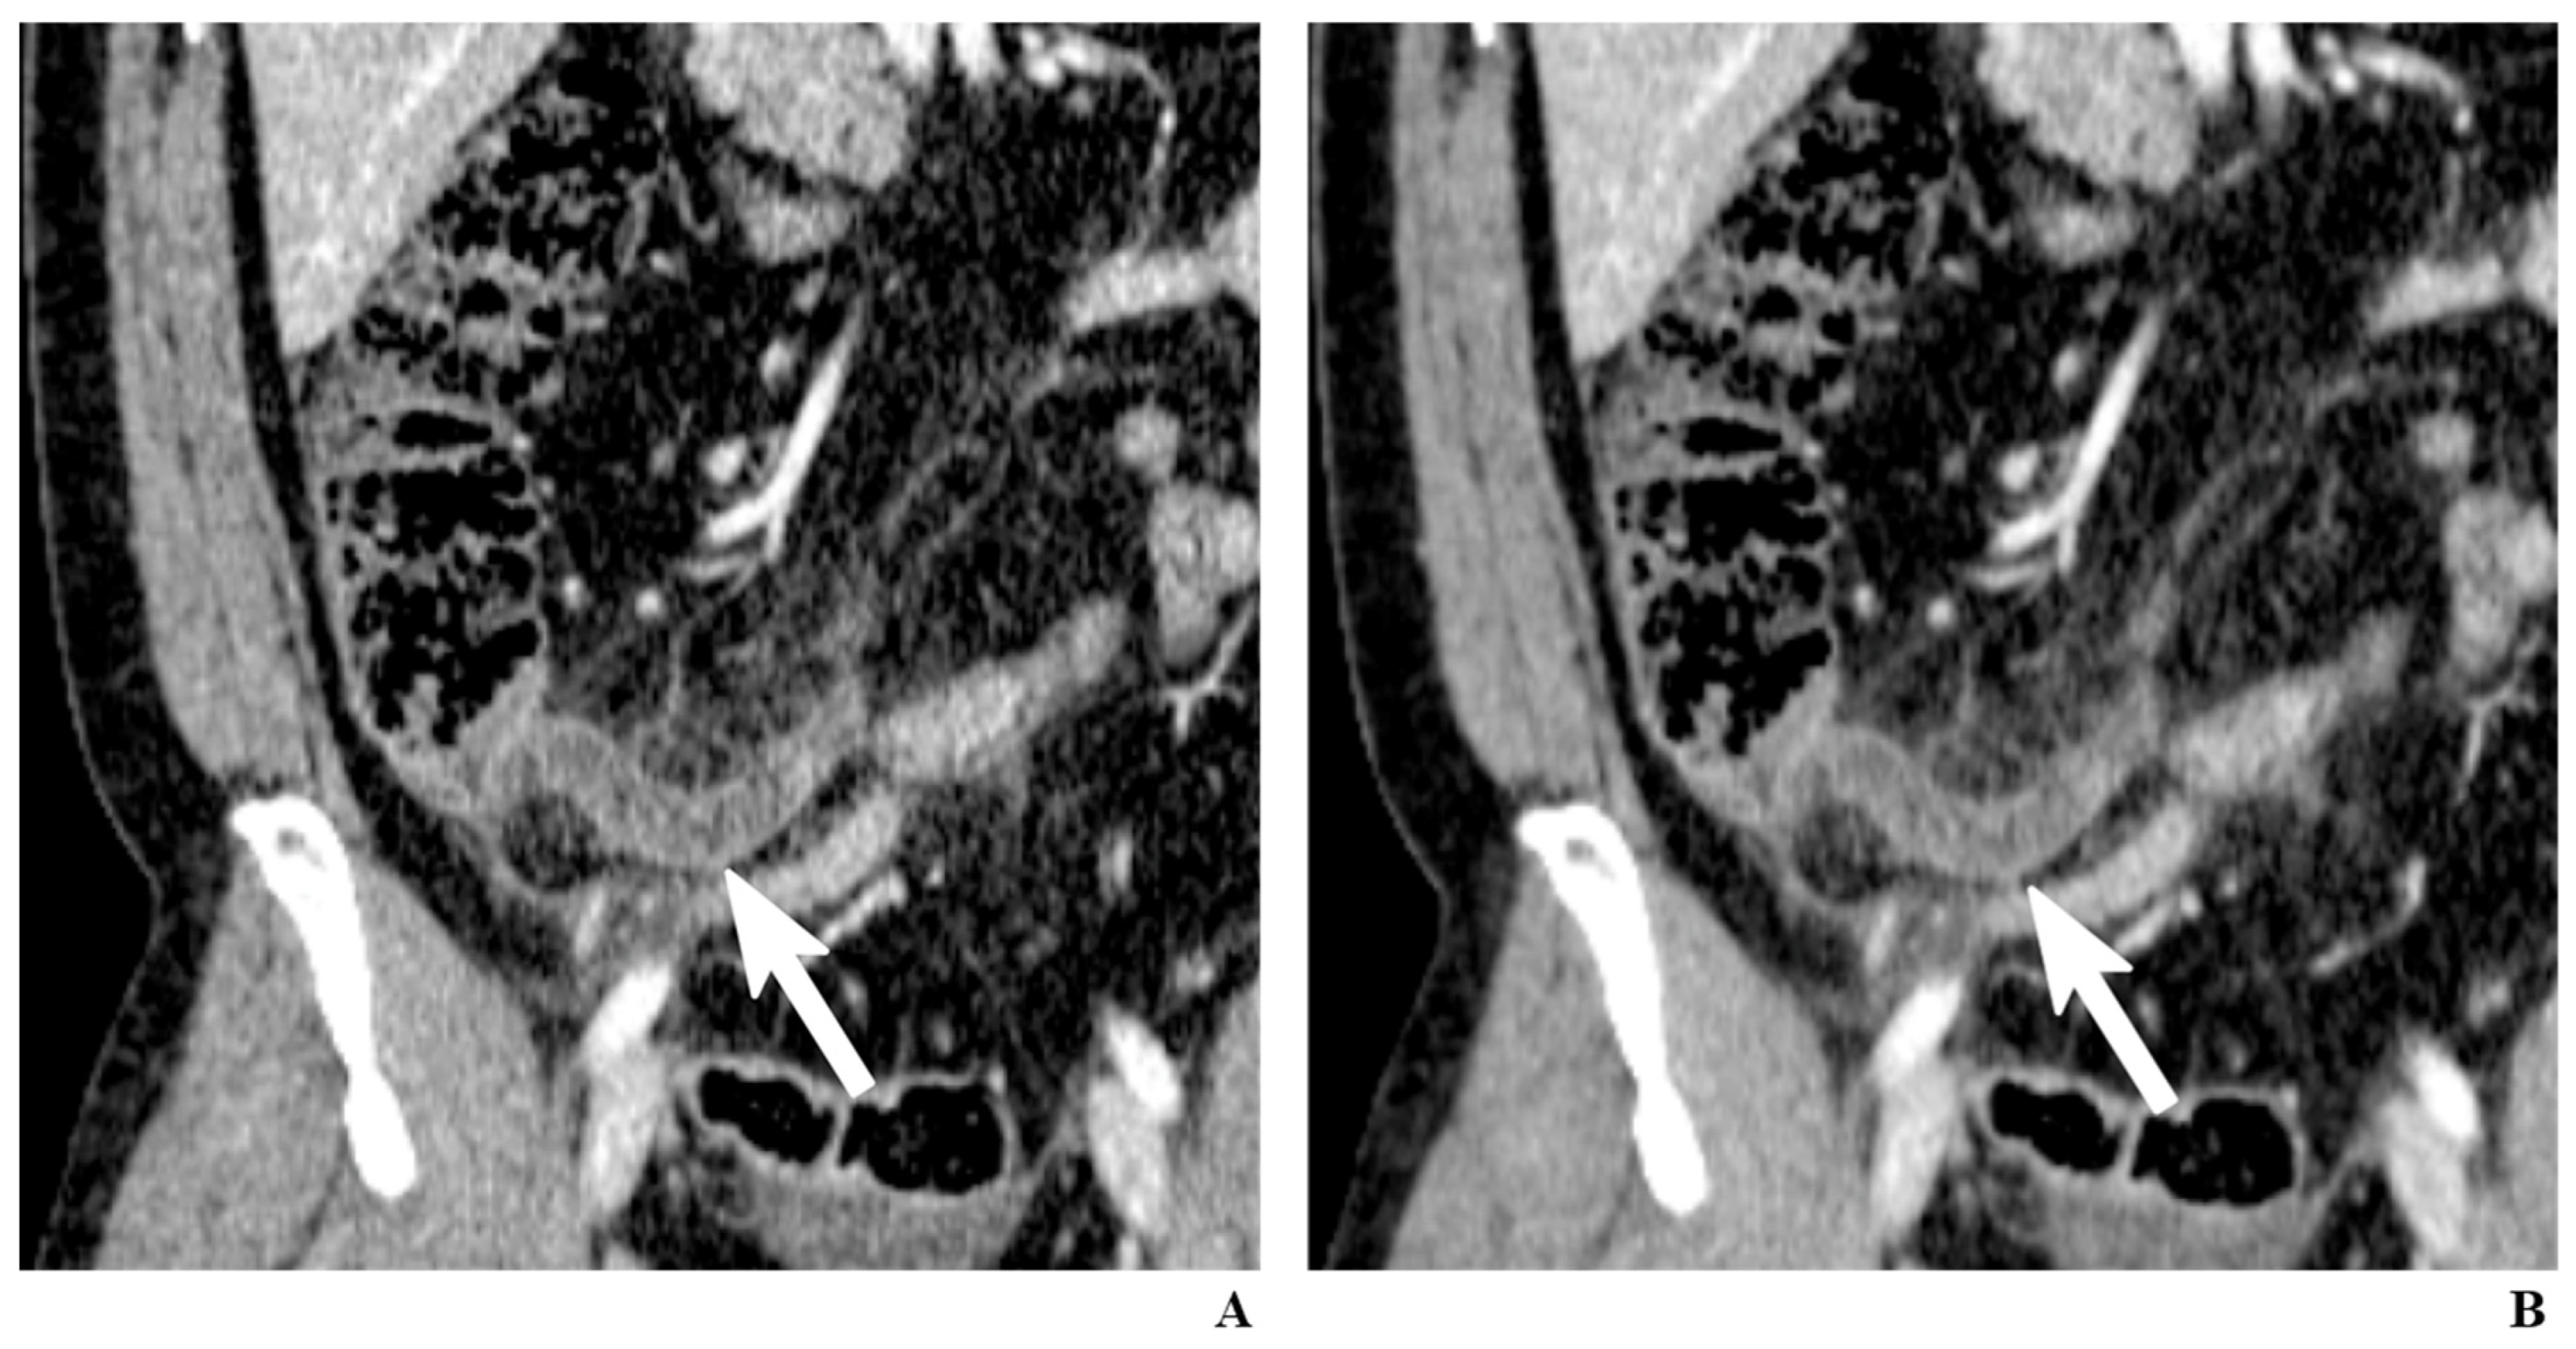

2.10. Sliding-Slab Averaging Technique